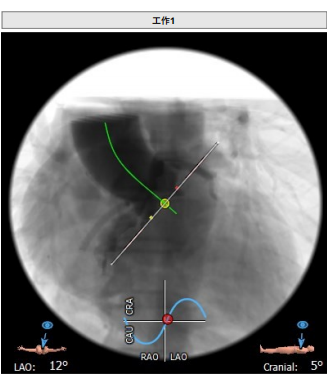

工作体位:LAO:12°CRA:5°,左冠切线位:LAO:26° CRA:19°